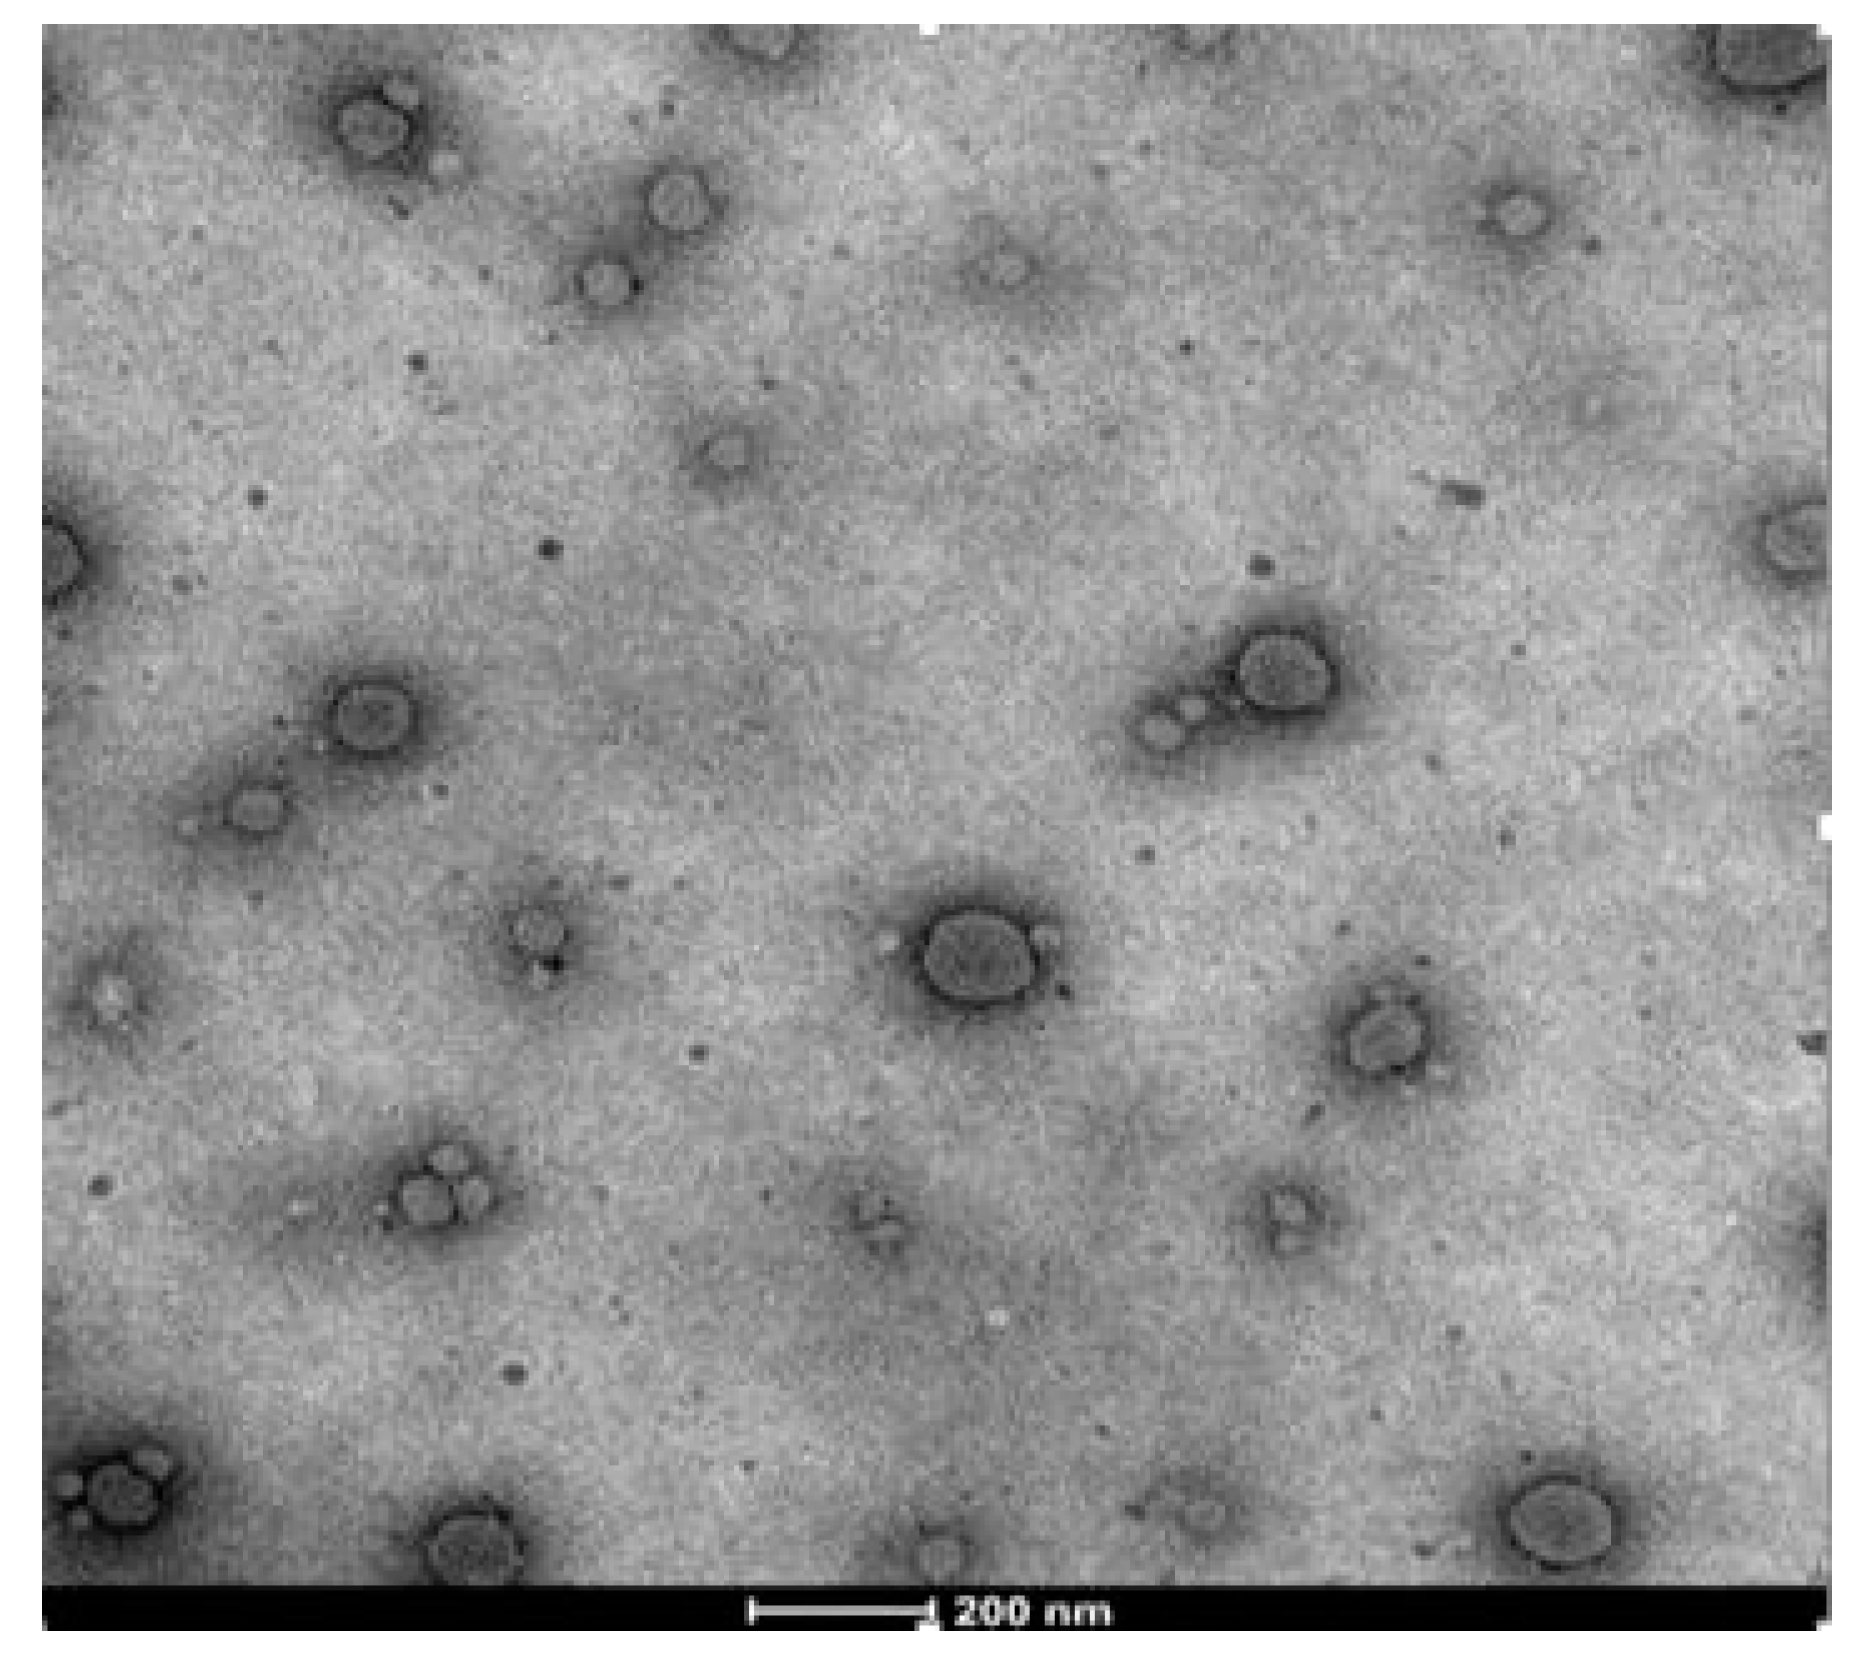

2.7.6. Transmission Electron Microscopy

3.6.5. Transmission Electron Microscopy